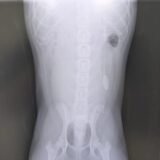

腹腔鏡手術は、高精細なカメラで体内を拡大して観察しながら、 精密な操作を可能にする先進的な外科技術です。

お腹を大きく開けることなく、 体内の様子を詳細に把握できるため、 より安全で正確な処置が期待できます。例えば、 お腹の中に隠れたままの精巣(潜在精巣)の摘出や、 診断が難しい内臓の組織検査(生検)など、 幅広い分野でその真価を発揮します。